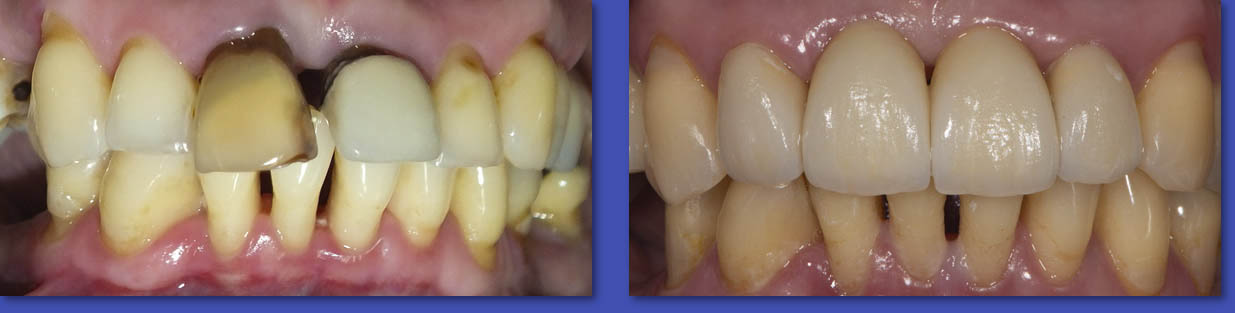

10. REHABILITACIÓN ORAL

La rehabilitación oral es una especialidad dentro de la odontología que combina en forma integral las áreas de prótesis fija, prótesis removible, operatoria, oclusión e Implante dental, que realiza el diagnóstico y plan de tratamiento adecuado al paciente de alta complejidad que requiere recuperar su salud bucal a través de las técnicas más modernas de rehabilitación. A su vez, establece estrecha relación con las demás disciplinas de la odontología, como periodoncia, endodoncia y ortodoncia.

ANTES

DESPUÉS